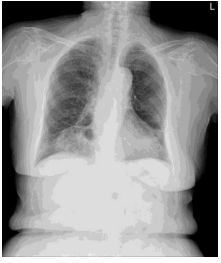

4. 39 y/o female, productive cough for 2 months